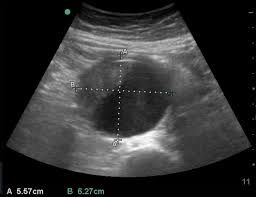

Should you use A or B used to measure the aorta?

A.